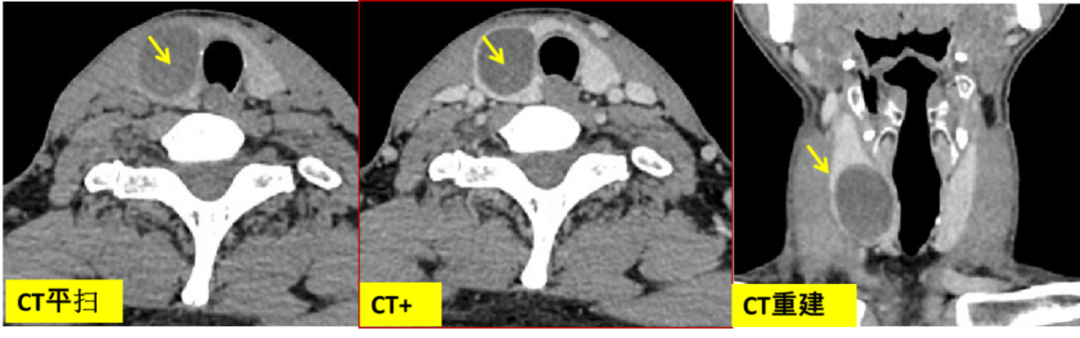

CASE 25

甲状腺左侧叶髓样癌,平扫边界清晰,增强后边界模糊